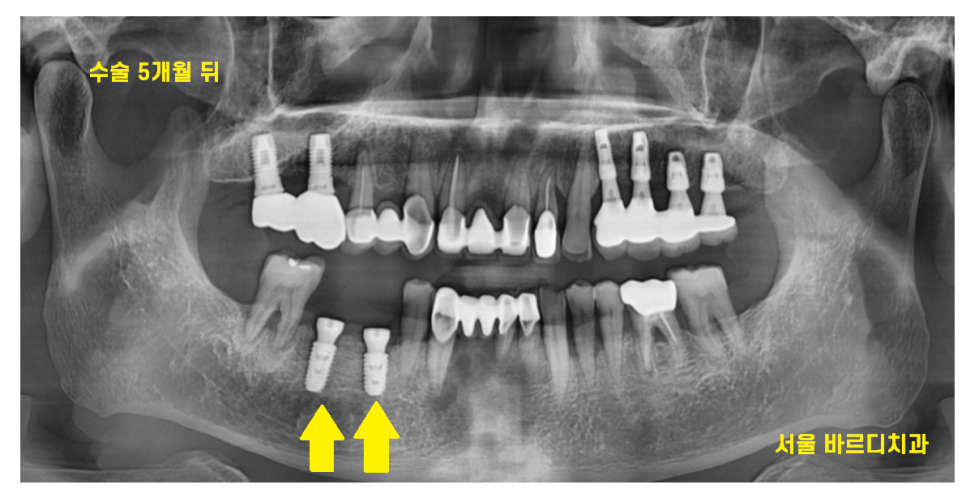

일반적으로는 아래 어금니는 3개월 뒤에

머리를 완성해드리지만

치아 욱신거림의 원인이

잇몸 이었던만큼

5개월정도

충분히 기다린 후 보철을 만들었습니다 .